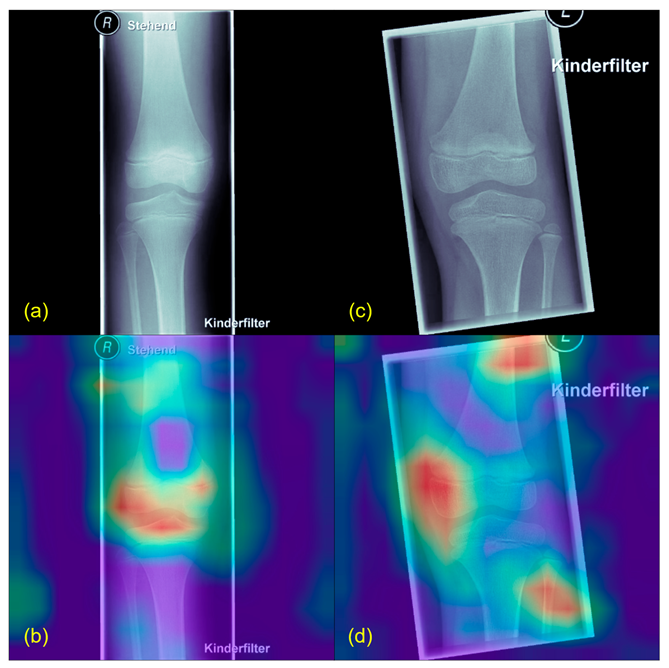

2.5. Plausibility